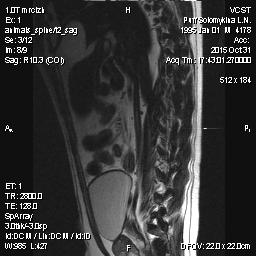

Мопс 6 лет - межпозвоночная грыжа - 10003.jpg

Мопс 6 лет - межпозвоночная грыжа - 10003.jpg (14.13 КБ) 768 просмотров